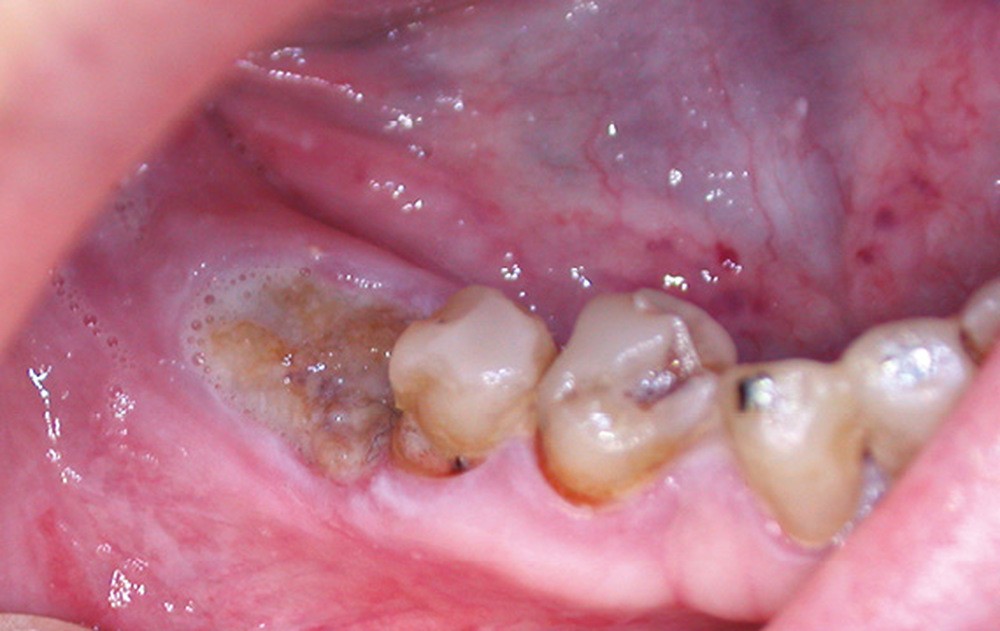

Un contrôle à la fréquence de 4 à 6 mois devra être instauré. La fréquence sera adaptée à l’état bucco-dentaire et à l’appréciation des facteurs locaux de susceptibilité du patient (risque carieux, biotype parodontal). La motivation à l’hygiène et l’efficacité du contrôle de plaque devront être entretenues. Les soins conservateurs précoces seront bien entendu privilégiés. Dans ce contexte, il ne faudra pas hésiter à conserver des dents d’une valeur intrinsèque faible pour éviter le recours à un geste chirurgical. En cas de carie délabrante ou de mobilité modérée, les soins conservateurs devront être privilégiés (endodontie, contentions). En cas d’infection, un traitement conservateur devra également être envisagé (fig. 2).

La priorité devra être donnée à la suppression de la composante infectieuse. Ainsi, pour éviter une extraction, il pourra être légitime de préconiser la conservation d’une dent à l’état de racine sur laquelle le traitement endodontique aura permis la stérilisation du foyer infectieux. Cependant, ce traitement conservateur ne sera retenu qu’à condition de pouvoir conserver durablement cette racine par une obturation étanche à l’aide d’un matériau de reconstitution définitif. Toutefois, pour contrôler l’infection, l’extraction pourra être nécessaire d’emblée ou en cas d’échec d’un traitement conservateur.